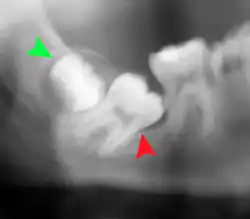

Impacted wisdom teeth are often described by the direction of their impaction (forward tilting, or mesioangular being the most common), the depth of impaction and the age of the patient as well as other factors such as pre-existing infection or the presence of pathology (cysts, tumors or other disease).[5]: 143–144 Each of these factors is used to predict the difficulty (and rate of complications) when removing an impacted tooth, with age being the most reliable predictor[8] rather than the orientation of the impaction.[9]

Another classification system often taught in U.S. dental schools is known as Pell and Gregory Classification. This system includes a horizontal and vertical component to classify the location of third molars (predominately applicable to lower third molars): the third molar's relationship to the level of the teeth already in the mouth, being the vertical or x-component and to the anterior border of the ramus being the horizontal or y-component.[10]